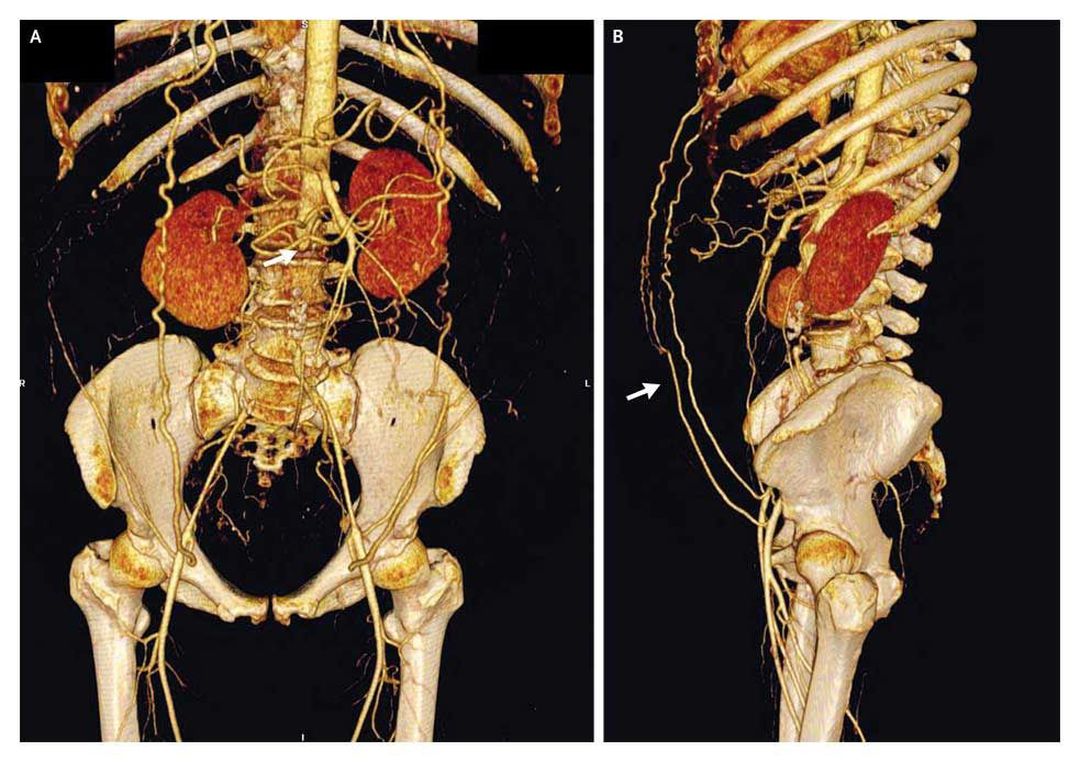

A 55-year-old woman awoke with an acute onset of bilateral leg numbness and weakness. Initial evaluation and lumbar magnetic resonance imaging, which was performed to assess the patient for disk disease, showed no cause for her symptoms, but her ankle pulses were noted to be diminished. The patient smoked cigarettes and had untreated hyperlipidemia; she reported that during the previous year, she had had bilateral buttock and thigh pain on walking 300 m. Her renal function was normal. Computed tomographic angiography showed complete occlusion of the infrarenal abdominal aorta (Panel A, arrow). A lateral view showed collateral blood flow from both internal thoracic arteries through subcutaneous epigastric abdominal vessels to the external iliac arteries (Panel B, arrow). Treatment included antiplatelet and statin therapy, successful smoking-cessation intervention, and exercise rehabilitation for peripheral artery disease. At 4 months, the patient's pain-free and maximal walking distances had improved. Distal aortic occlusion occurs most commonly in young women with dyslipidemia who smoke. Aortic atherosclerosis (a chronic process) with subsequent aortic occlusion (an acute thrombotic process) can occur without major threat to leg survival and function when collateralization is extensive, as was the case in this patient. Medical therapy can be effective, thus avoiding the risk of surgical revascularization. At her last visit, the patient had not required revascularization and was able to perform normal activities of daily living. Alan T. Hirsch, M.D. Michael D. Miedema, M.D. Abbott Northwestern Hospital, Minneapolis, MN 55407 source: nejm.org